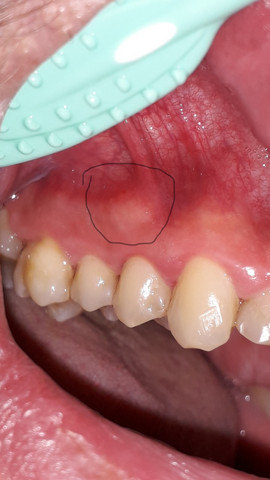

Beule am zahnfleisch ohne schmerzen. Die braucht sie dann auch. In diesen Fällen sollte man am besten zwei bis drei Tage abwarten und schauen ob sich die Situation bessert. Das sieht nach einer stark entzündeten Zahnfleischtasche aus.

Am Zahn und Zahnfleisch können viele Probleme entstehen. Die beuele ist vermutlich ein sich ausbildender abszeß der von alleine nicht besser wird auch die schmerzen werden nicht besser. Der wird die Stelle behandeln und ihr wahrscheinlich Antibiotika verschreiben.

Weitere Auslöser können sein. Eine Eiterbeuleentsteht durch die Entzündung im Knochen und am Zahn. Probleme am Zahn wie Zyste Fistel Eiter Schwellung.

Zahnentzündung apikal bedeutet dass sich die Entzündung an der Wurzelspitze befindet. Das Anschwellen vom Zahnfleisch und evt. Wenn die Wurzel am Zahn entzündet ist macht sich dies meist bemerkbar durch die Schmerzen und ein leichtes anschwellen vom Zahnfleisch.

Dehnt sie sich bis zum Kieferknochen aus heißt. Deshalb empfindet der Betroffene keine Schmerzen obwohl sich die Entzündung mit großer Wahrscheinlichkeit schon tief in den Kiefer hinein vorgearbeitet hat. Ein traumatischer Zahnunfall oder eine Verletzung.

Entweder wurde das Zahnfleisch durch mechanische Reize verletzt oder eine Infektion mit Viren Bakterien oder Pilzen ist schuld an der Entzündung. Die Beule ist unnachgiebig aber sie ist ja noch ein Kind. Diese Bakterien können einen Abszess verursachen selbst wenn die Zähne gesund und frei von Löchern sind.

Mit der richtigen Betäubung ist die Behandlung vom Zahn ohne Schmerzen. Eine Schwellung des Zahnfleisches ist ein Anzeichen für eine Entzündung.